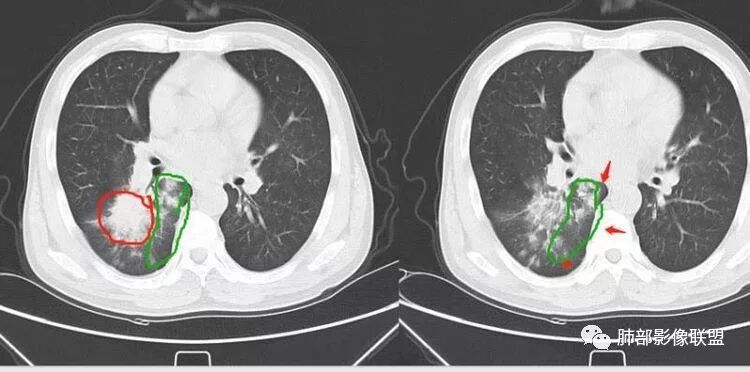

远端确实有膨隆,边缘凹凸不平,换个角度,这个病灶紧贴着斜裂外带。

南边:紧贴着斜裂过来的一个病灶,它的特点是:外围大,内带小。它整个下叶背段体积与对侧相比稍微缩小一点,但是缩小地不是很厉害。外支朝前下走了,仔细看血管,肺动脉走行自然,直达远端。远端实变区是肉芽肿成分,稍微有一点低密度,没有明显坏死,稍微有一点点坏死。而且附近有很多卫星灶,附近很多斑片影,有一些明显有气道壁增厚,细支气管炎的特点,还有就是下叶其他段很多斑片状影。换个角度,第一如果是肺癌,刚才看到PET-CT提示肺癌伴阻塞性肺炎,这个是不符合的。第二如果是肺癌阻塞性肺炎,近端血管肺动脉走行不会那么自然集聚的,这个是不符合的。理由是:如果这个病灶是肺癌,那么明显属于中央型肺癌,中央型肺癌的特点是近端大,远端小,近端是一个肿块,远端阻塞,远端阻塞是阻塞性炎症或者不张,它应该体积缩小,斑片状实变,不会这么密实。刚才有老师提到支气管,这个片有缺陷的地方,给的图像好像那层,如果把其他图像拿开再重叠一下。

如果是单纯看这幅图像,会觉得背段外侧支气管分支堵塞的,但是看下面这层图

南边:你就发现外侧支气管朝下走的分支非常自然,通畅的。

南边:这个肺门区,11区和7区都有一些淋巴结,淋巴结的形态不是类圆形,而是梭形的。这个病灶给的图比较少,个人倾向,第一强化非常均匀,肉芽肿性病变;第二,里面血管走行非常自然,远端大近端小,倾向炎性,特别是下面还有斑片状影,非阻塞远端,支气管远端病灶下叶背段,其他段也有,所以我倾向炎性;另外,它里面整个走行符合支气管树爬行征,我倾向结核可能,首先我定在炎性,其次有没有结核的可能。